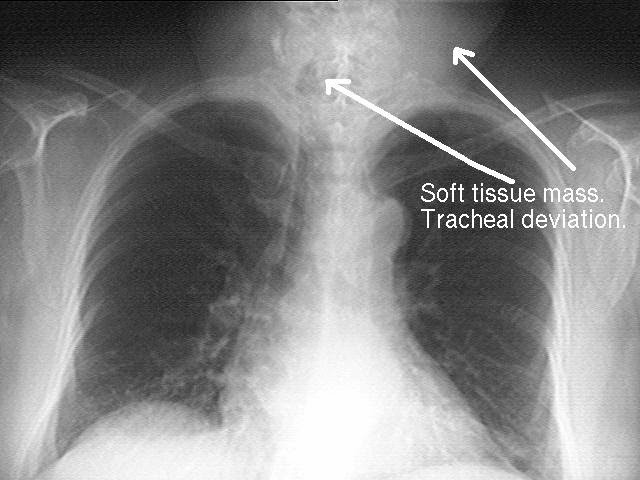

Ακτινογραφία θώρακος: Η ακτινογραφία αυτή γίνεται για εντοπισμό πιθανής διήθησης της ασθένειας στους λεμφαδένες του θώρακα.